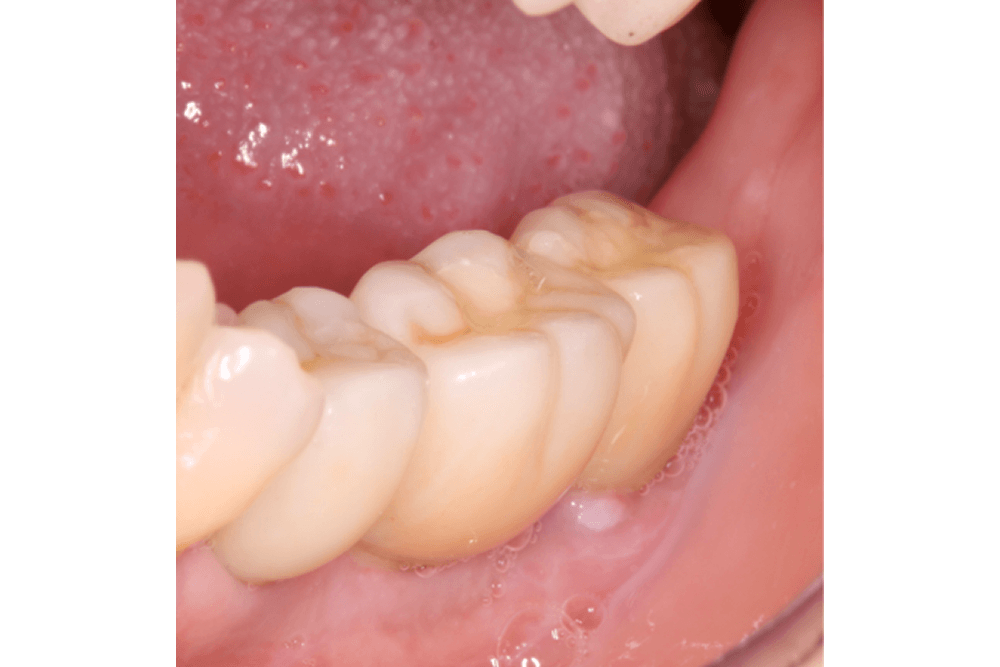

Próteses Total

Conhecidas também como Dentaduras, são próteses removíveis, indicadas para pacientes que perderam todos os dentes da arcada superior e/ou inferior. São confeccionadas através de moldagens que reproduz a anatomia da mucosa da arcada do indivíduo. Este método de tratamento relativamente rápido é também de baixo custo e capaz de devolver estética, e função mesmo sendo removível e apenas suportada pela mucosa oral.